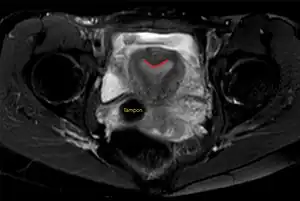

| Arcuate uterus (marked in red) seen on MRI | |

A transvaginal ultrasound can reveal the condition.

Helpful techniques to investigate the uterine structure are transvaginal ultrasonography and sonohysterography, hysterosalpingography, MRI, and hysteroscopy. More recently 3-D ultrasonography has been advocated as an excellent non-invasive method to delineate the condition.[5]